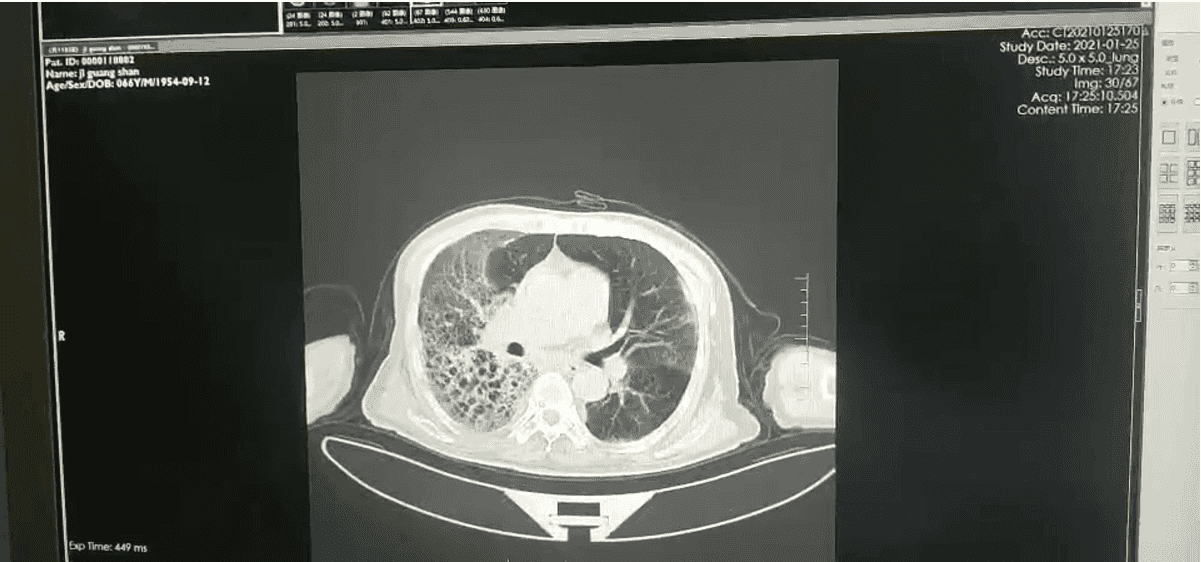

入院第六天我们通过 mNGS 检测出患者的血液和痰液中存在羊流产衣原体,可确认为肺炎的病原体但是由于衣原体感染大多都是混合感染,因此我们并没有停止帕拉西林钠他唑巴坦钠的使用在治疗第 10 天,我们复查了胸部 CT,结果示两肺间质性炎症较前改善,两肺少量胸腔积液(图 2)。

图 2:入院第十天胸部 CT,两肺间质性炎症较前改善,两肺少量胸腔积液患者因为检测出了乙肝小三阳和梅毒特异性抗体阳性,因此患者转院前往传染病医院进一步治疗,嘱患者出院后口服莫西沙星和克拉霉素抗感染治疗我们在患者出院二十天后进行随访。